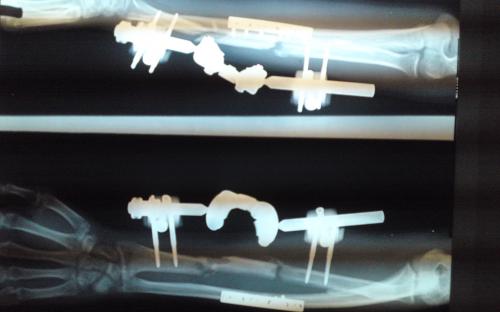

Άντρας 21 ετών υπέστη διπολικό κάταγμα της κερκίδας και κάταγμα της ωλένης, που αντιμετωπίστηκε σε περιφεριακό νοσοκομείο. 9 μήνες μετά διαπιστώθηκε ψευδάρθρωση της κερκίδας με οστικό απόλυμα 6,5 εκ. Αντιμετωπίστηκε με τη χρήση αγγειούμενης περόνης, η οποία γεφύρωσε το οστικό έλλειμμα της κερκίδας.